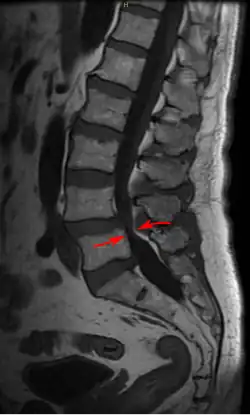

Lumbar vertebra showing central stenosis and lateral recess stenosis.

MRI of a lumbar spinal stenosis L4-L5. L4-L5 antherolisthesis of grade I. Hypertrophy of interspinous ligaments in relation to Baastrup's disease. 67 years old man.